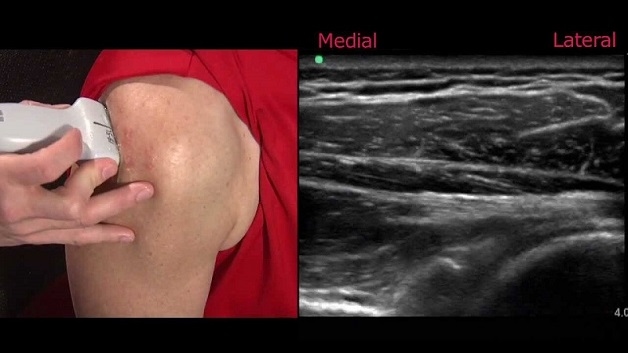

Bệnh nhân khi thực hiện kỹ thuật siêu âm này thường ở tư thế ngồi thấp hơn bác sĩ. Bên cạnh đó, người bệnh có thể được yêu cầu thực hiện một số động tác trong quá trình siêu âm nhằm mang lại những hình ảnh chính xác nhất. Bác sĩ siêu âm sẽ sử dụng một đầu dò đặc biệt phát ra sóng âm tần số cao để có thể khảo sát ở cả hai bên vai và bắt đầu từ bên lành hoặc có ít triệu chứng hơn.

Siêu âm cho khớp vai sẽ giúp bác sĩ thấy được hình ảnh của các gân chóp xoay và ngoài chóp xoay (bao gồm các gân cơ nhị đầu, gân cơ trên, dưới gai, gân dưới vai, gân cơ tròn bé), các khớp (bao gồm các khớp cùng vai – đòn, khớp ổ chảo – cánh tay, khớp ức đòn) và các dây chằng ổ khớp.